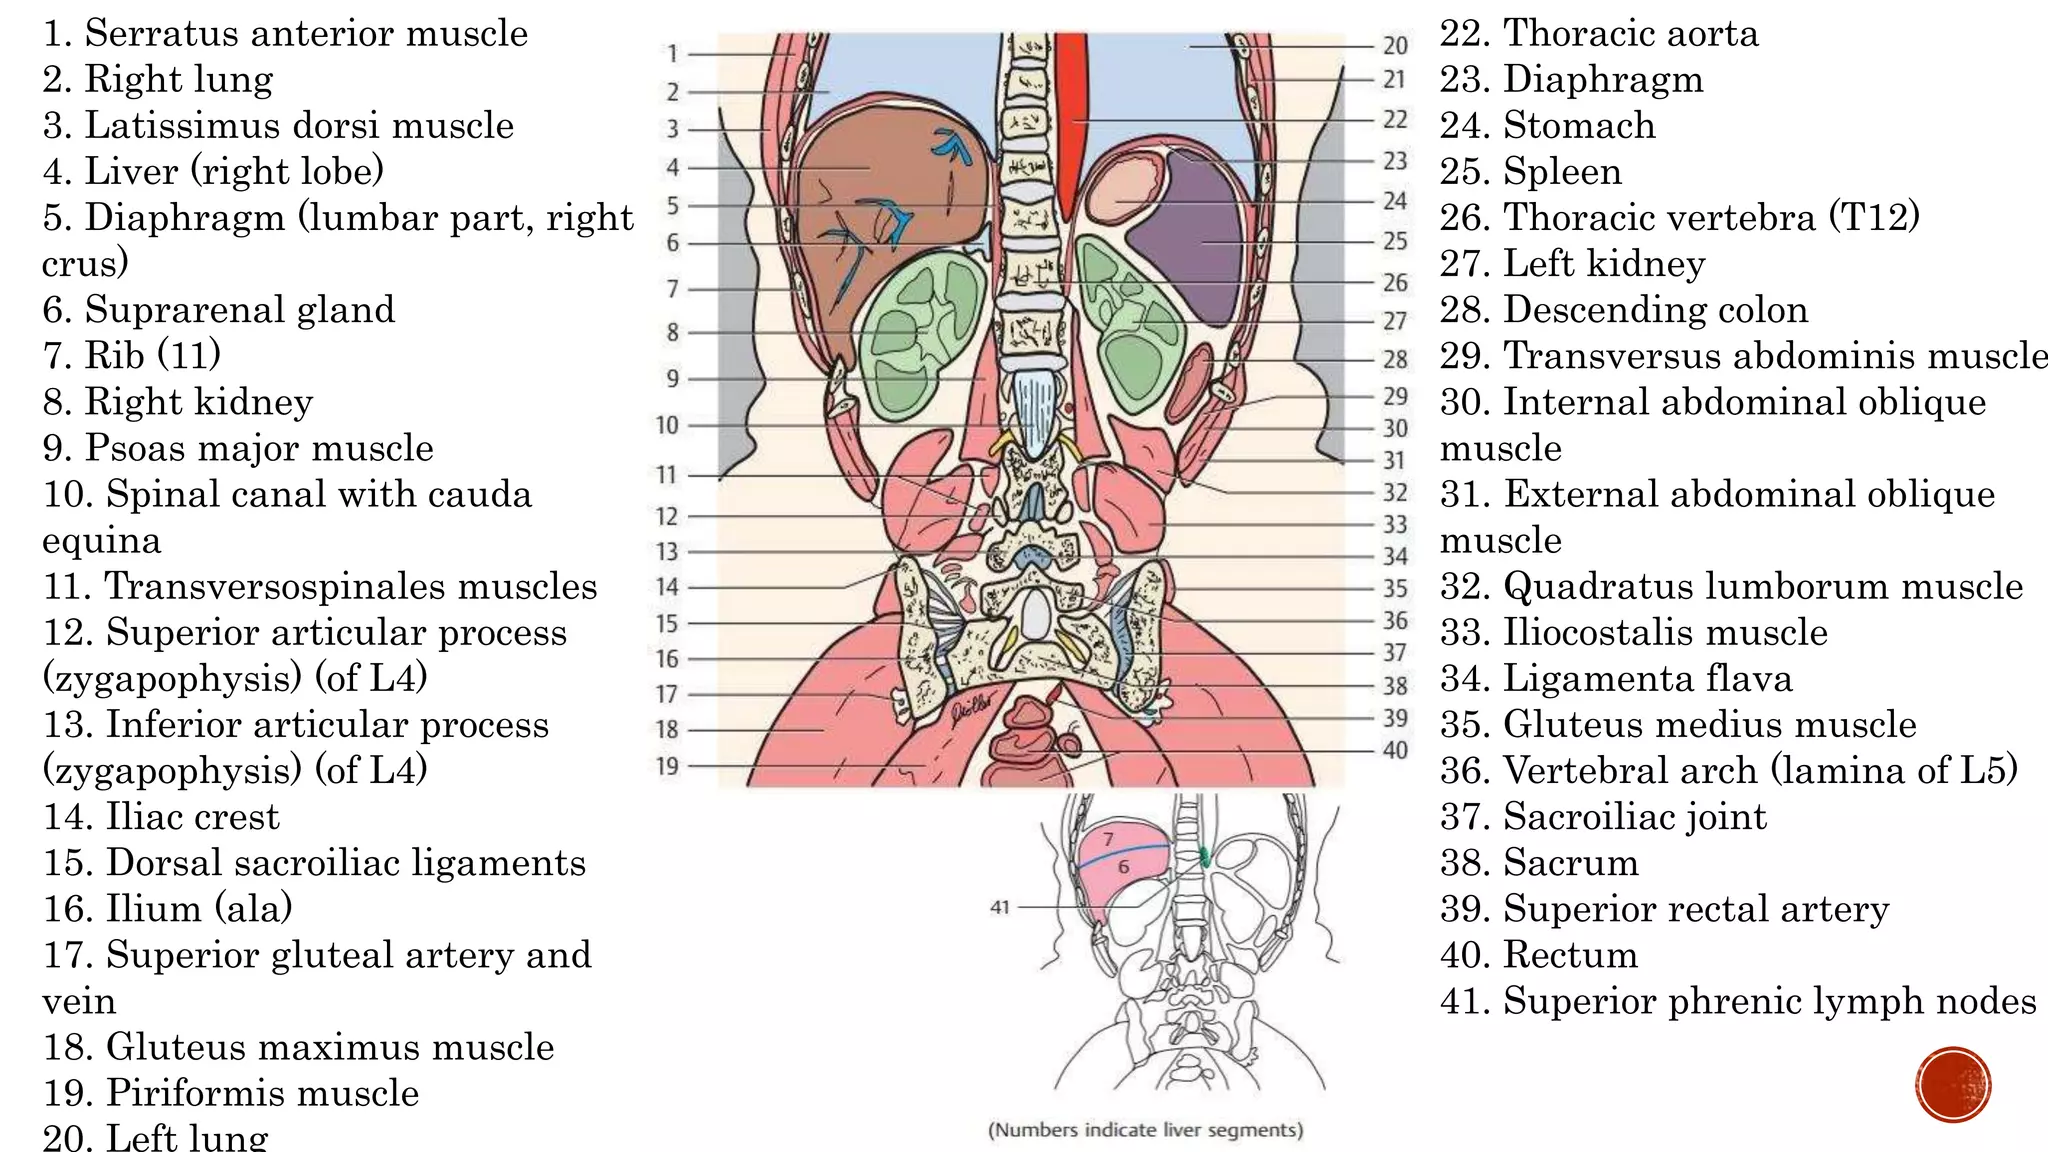

The document describes the anatomy of the abdomen and pelvis region of the human body. It lists over 40 structures and their locations, including major organs like the liver, kidneys, intestines, blood vessels and muscles of the abdominal wall and pelvis. The structures are grouped into sections focusing on different anatomical areas like the abdomen, retroperitoneum, pelvis and gluteal region.